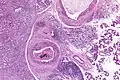

Their histologic appearance is similar to ductal breast carcinoma.

Very low mag. -